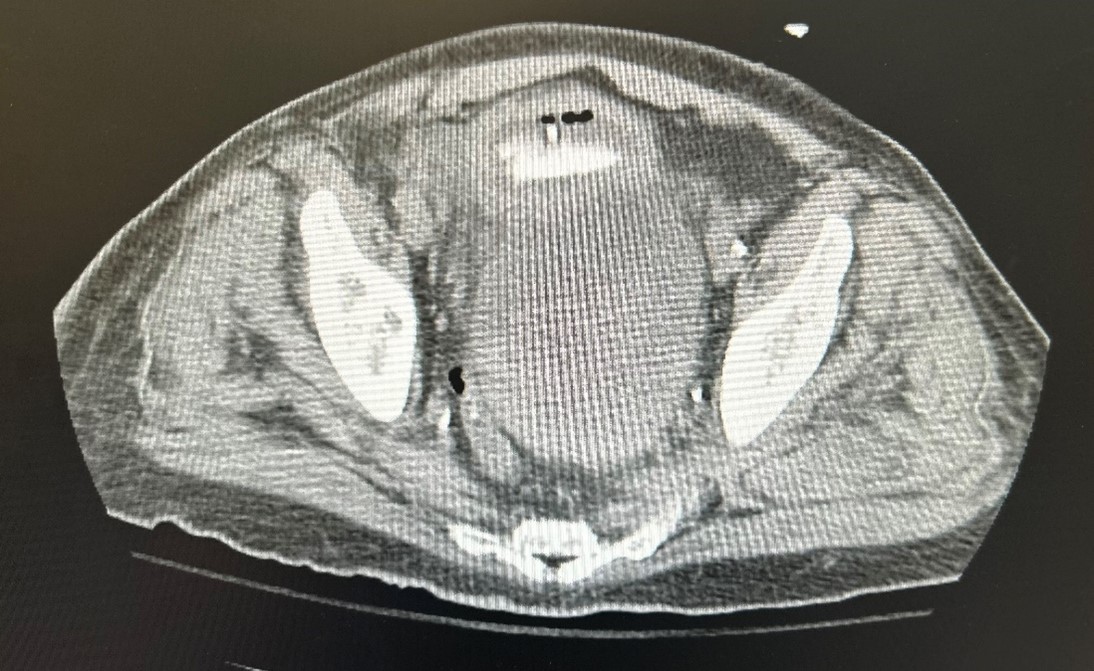

Case Presentation: A 70-year-old male with a history of hypertension, hyperlipidemia, cerebrovascular accident (CVA), benign prostatic hyperplasia (BPH), anemia, atrial fibrillation (AFib), coronary artery disease (CAD), and gastroesophageal reflux disease (GERD) presented with gross hematuria and abdominal pain. He had recently been discharged after treatment for a subdural hematoma and had a long-term Foley catheter placed due to subdural hematoma, removed the day before this admission. The patient was also being treated for a Pseudomonas-positive urinary tract infection (UTI) from a prior hospitalization. On presentation of this admission, he denied chest pain, shortness of breath, fever, or chills but reported abdominal pain and dysuria. Urology was consulted, and continuous bladder irrigation (CBI) was initiated. Initial CBC revealed anemia, Hgb 6.0, due to acute blood loss, and the patient was transfused with 4 units of packed red blood cells. Urinalysis showed a UTI with positive nitrates, leukocytes, and blood. Head CT confirmed a previous craniotomy with residual fluid in the subdural space. A bladder ultrasound suggested a diverticulum, and CT imaging revealed a fistula and two large masses, one near the bladder and another at the left iliac wing. The patient developed significant hematuria, requiring two additional blood transfusions. Initially, it was believed that these masses were sarcomas in nature. A CT-guided biopsy confirmed multiple myeloma, supported by electrophoresis. Given the complexity, the patient was transferred to a tertiary care facility for further management following a multidisciplinary conference.